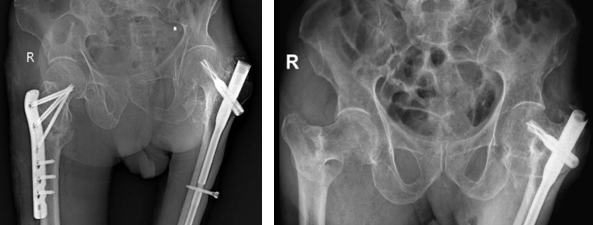

• Phương pháp kết hợp xương bằng nẹp vít: Phương pháp này được chỉ định cho trường hợp gãy xương đơn giản. Các loại nẹp được sử dụng phổ biến gồm: nẹp khóa đầu trên xương đùi, nẹp gấp góc DHS …​​​​​​​

Nẹp DHS

Nẹp khoá đầu trên xương đùi